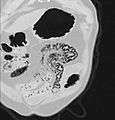

Pneumatosis intestinalis (also called intestinal pneumatosis, pneumatosis cystoides intestinalis, or pneumatosis coli) is pneumatosis of an intestine, that is, gas cysts in the bowel wall.[1] As a radiological sign it is highly suggestive for necrotizing enterocolitis. This is in contrast to gas in the intestinal lumen (which is relieved by flatulence). In newborns, pneumatosis intestinalis is considered diagnostic for necrotizing enterocolitis, and the air is produced by bacteria in the bowel wall.[2] The pathogenesis of pneumatosis intestinalis is poorly understood and is likely multifactorial. PI itself is not a disease, but rather a clinical sign. In some cases, PI is an incidental finding, whereas in others, it portends a life-threatening intra-abdominal condition.